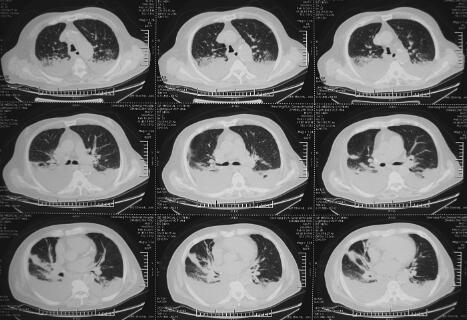

患者,男性,87岁。急性起病,主因“劳累后胸闷、气短2天,加重伴咳嗽、咳痰1天”于2011年2月18日收入急诊监护室。患者于2011年2月16日劳累后出现胸闷、气短,伴咳嗽、咳黄痰,可平卧,偶有夜间憋醒,休息后症状缓解,翌日劳累后再次出现上述症状,无心前区疼痛,无发热、寒战,无恶心、呕吐,无尿少,就诊于笔者医院,进行心脏超声检查:EF 40%,冠心病、心肌梗死表现、心功能减低,考虑心尖部室壁瘤形成,二尖瓣、三尖瓣及主动脉瓣反流(轻度);腹部超声:双侧胸腔积液,少量心包积液;双肺CT(图1):双侧胸腔积液,心胸比例> 0.5;院第2天胸片见图2。血液分析:白细胞9.34×109/L,中性粒细胞85.5%;心肌酶谱:肌钙蛋白0.144μg/L,磷酸肌酸激酶125U/L,磷酸肌酸激酶同工酶20U/L;B型尿钠肽8326pg/ml。既往史:冠心病病史10余年,自服阿司匹林、复方丹参滴丸、硝酸异山梨醇酯等,2010年7月急性心肌梗死经内科治疗后病情稳定;陈旧性脑梗死病史10余年、胃部分切除史20余年。

图1 入院第1天双肺CT:双侧胸腔积液、叶间裂积液